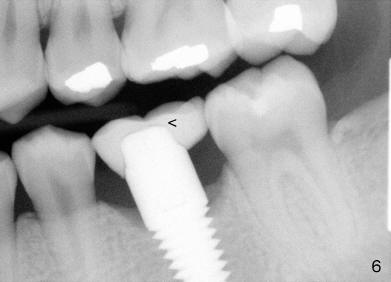

The buccal plate remains atrophic 7.5 months post cementation (Fig.9, as compared to Fig.5), while there is bone deposit next to the most coronal threads (Fig.10).

The crown was dislodged once and recemented with resin bonding.  If it recurs, check whether the abutment is loose and re-prepare the margin and deepen the retentive groove.